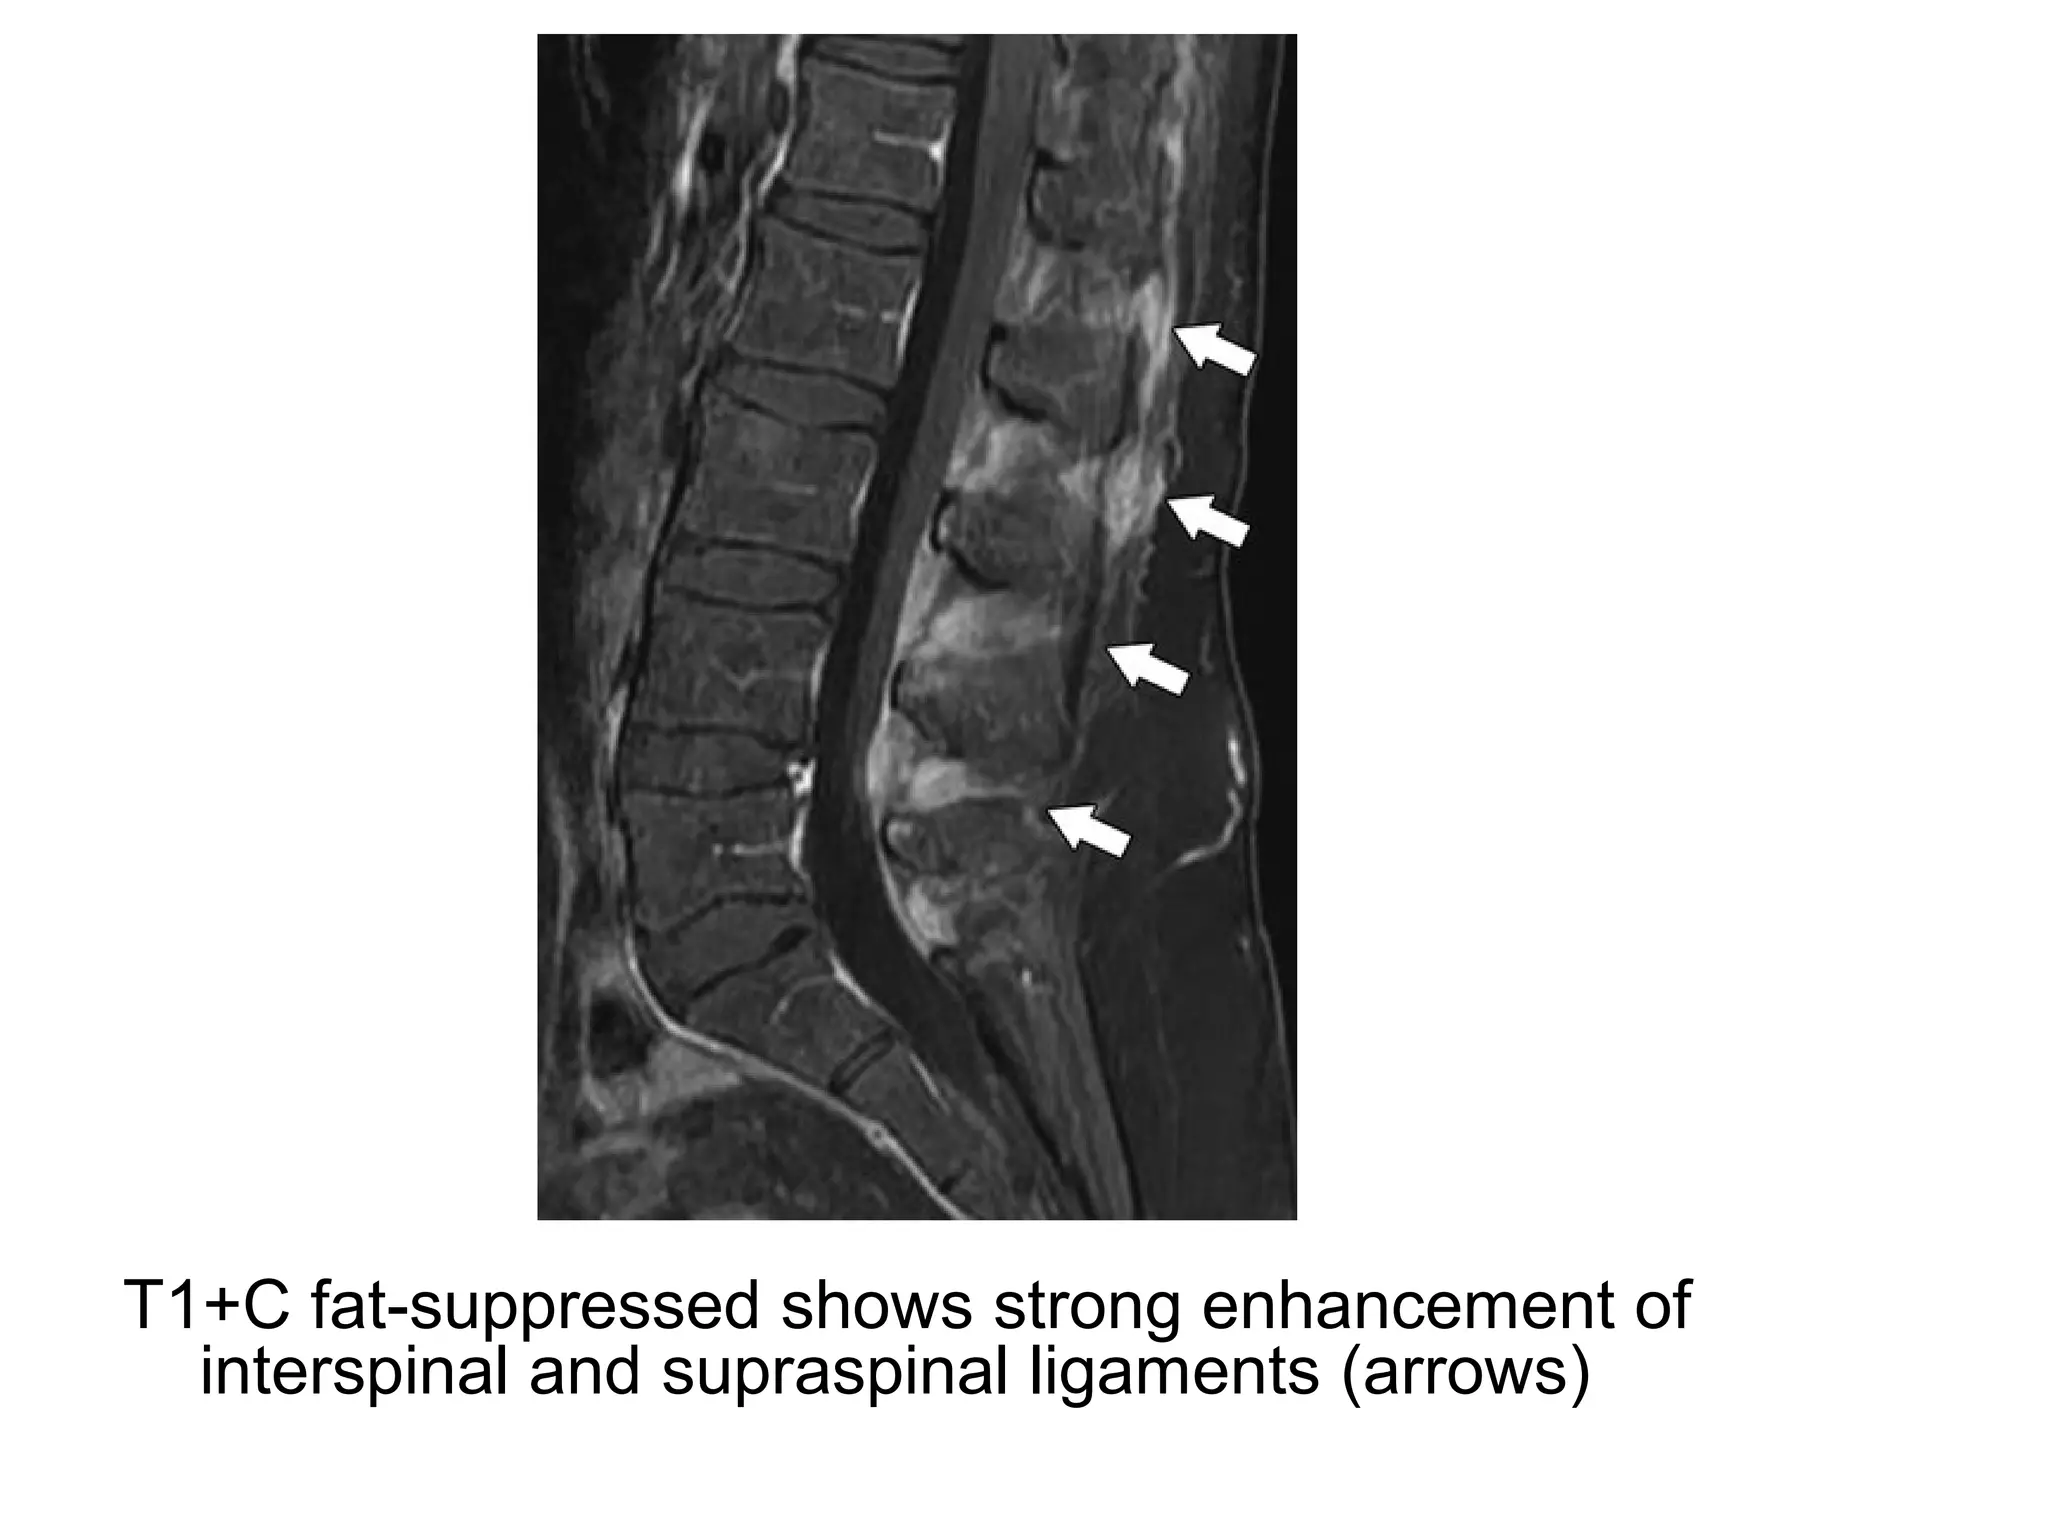

T1+C fat-suppressed shows strong enhancement of

interspinal and supraspinal ligaments (arrows)

4-True Ligamentous Inflammatory Involvement:

-Although ligamentous lesions are most commonly

confined to the bone insertions , they can also

involve other parts of the ligament ,

corresponding to true ligamentous inflammation

-T1+C fat-saturated is more sensitive than T2 or

STIR in the detection of this type of involvement

-All the vertebral ligaments may be affected , most

often the interspinal and the supraspinal

ligaments